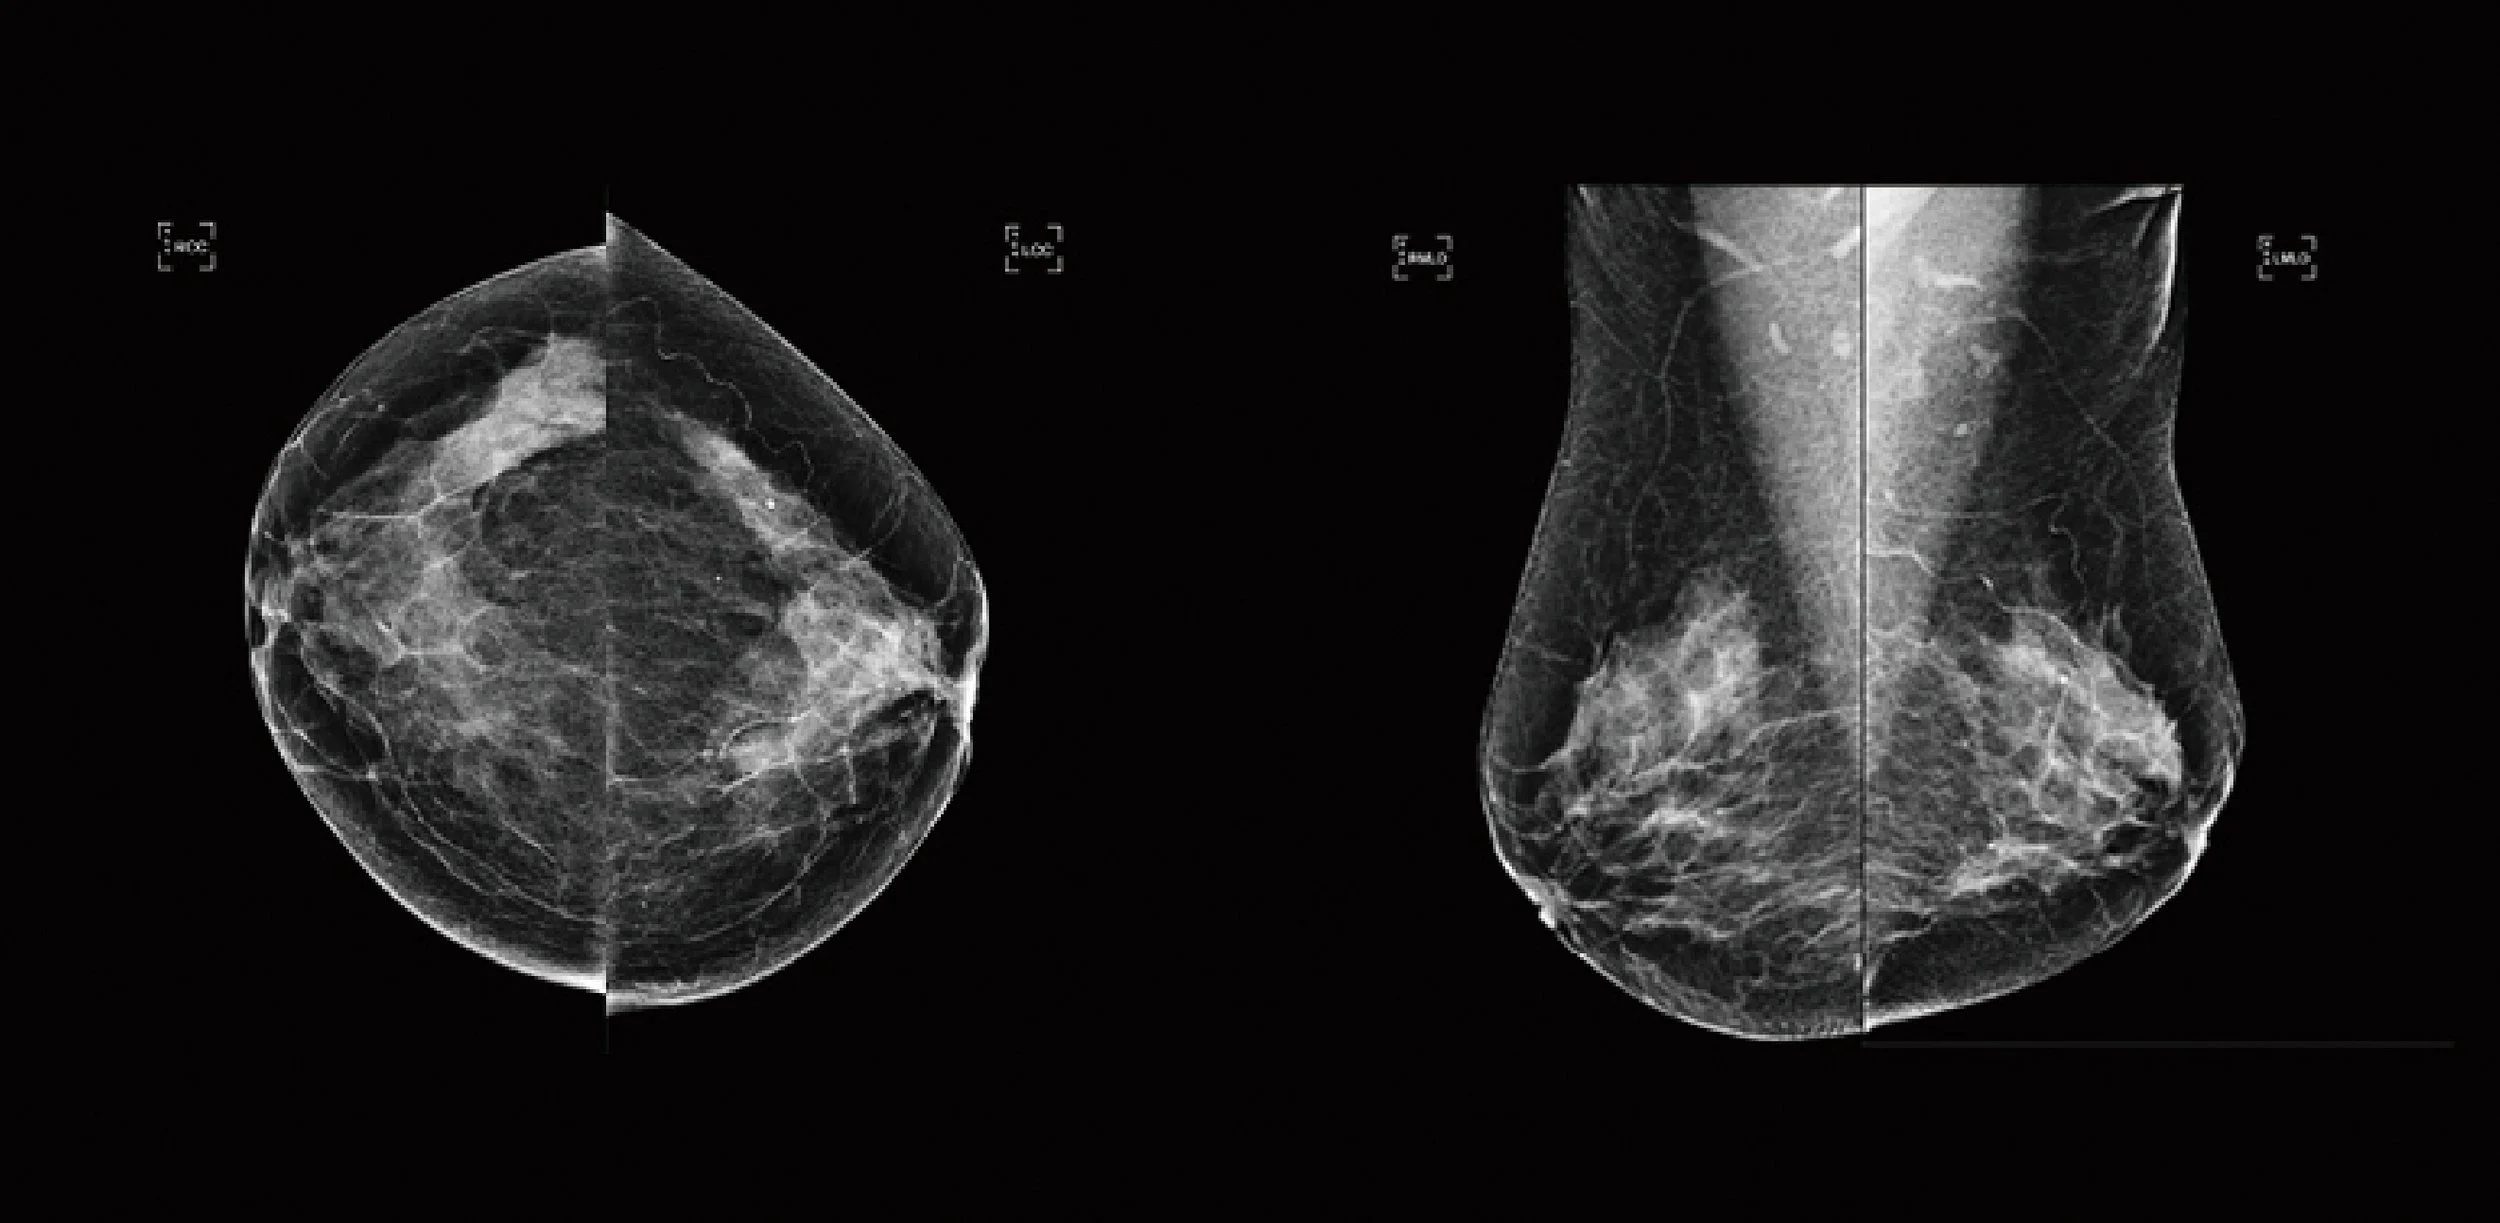

Figure 1: Radiologist review: no cancer detected.

Abnormality Score: 84

Figure 2: SecondReadAI™ review: suspicion of breast cancer detected (indicated by yellow highlighted area).